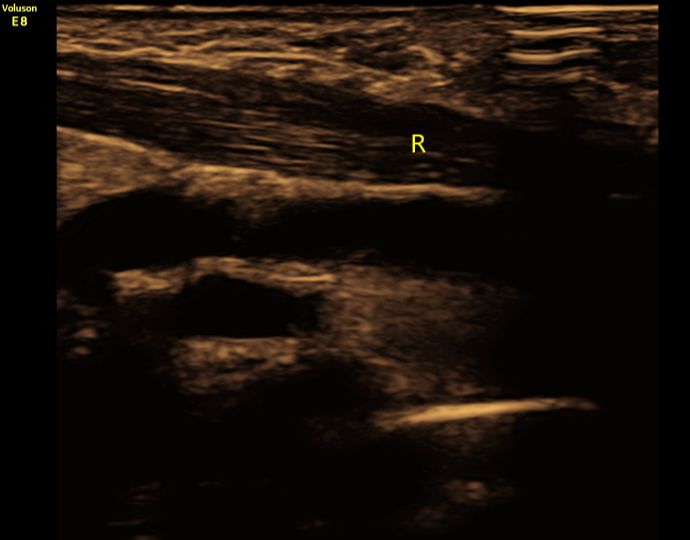

(图5:患儿三周后复查,右侧锁骨骨折断端已未见明显错位及成角,局部血肿已消失。)

新生儿锁骨骨折预后良好,一般无需特殊治疗,随着小儿的生长发育,肩部增宽,错位及畸形均可自行消失。